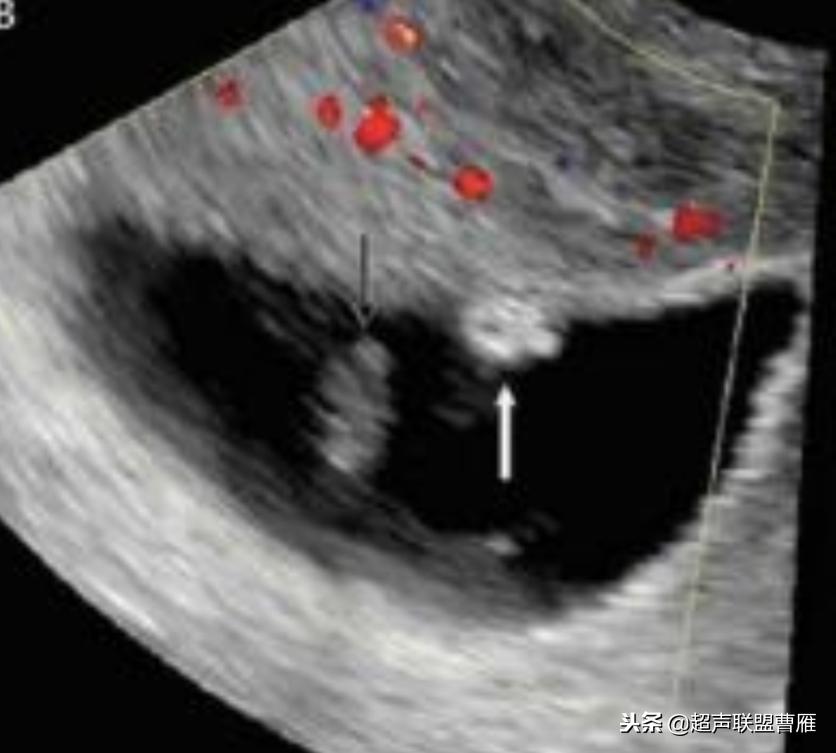

胎芽 卵黄囊 心管搏动信号

宫内早孕 (7周左右)